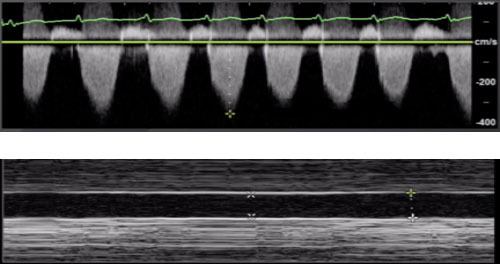

There are a number of different data points that can be collected that inform us of the function and loading conditions of the Right Ventricle (RV): Shape and size of the RV, Inferior Vena Cava (IVC), Tricuspid Angular Plane Systolic Excursion (TAPSE), and Right Ventricular Systolic Pressure (RVSP).

A global eyeball assessment of the shape and size of the RV is the most important initial competence, related to the RV, to develop as a point-of-care echocardiographer. For this more advanced tutorial, however, we will focus on TAPSE and RVSP; they are cited and applied frequently in clinical medicine, and they can be done with relative ease and applicability for making decisions at the bedside.